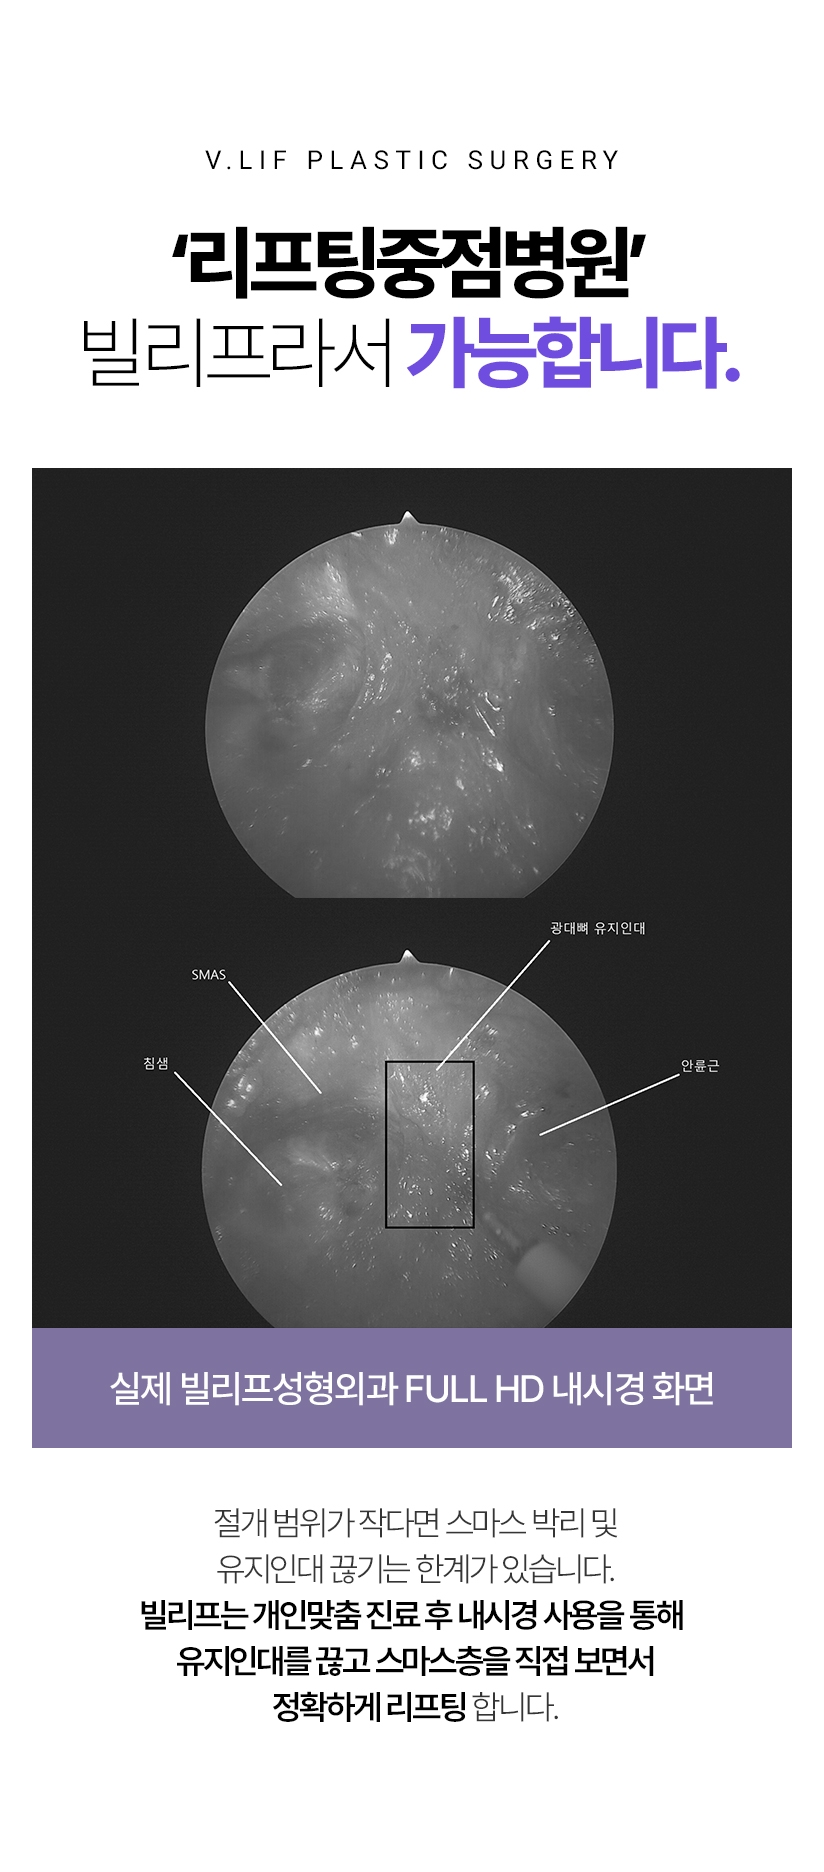

‘리프팅중점병원’ 빌리프라서 가능합니다. 절개 범위가 작다면 스마스 박리 및 유지인대 끊기는 한계가 있습니다. 빌리프는 개인맞춤 진료 후 내시경 사용을 통해 유지인대를 끊고 스마스층을 직접 보면서 정확하게 리프팅 합니다.